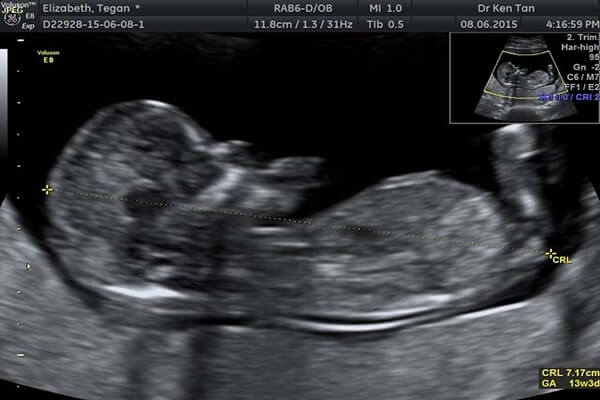

độ mờ da gáy